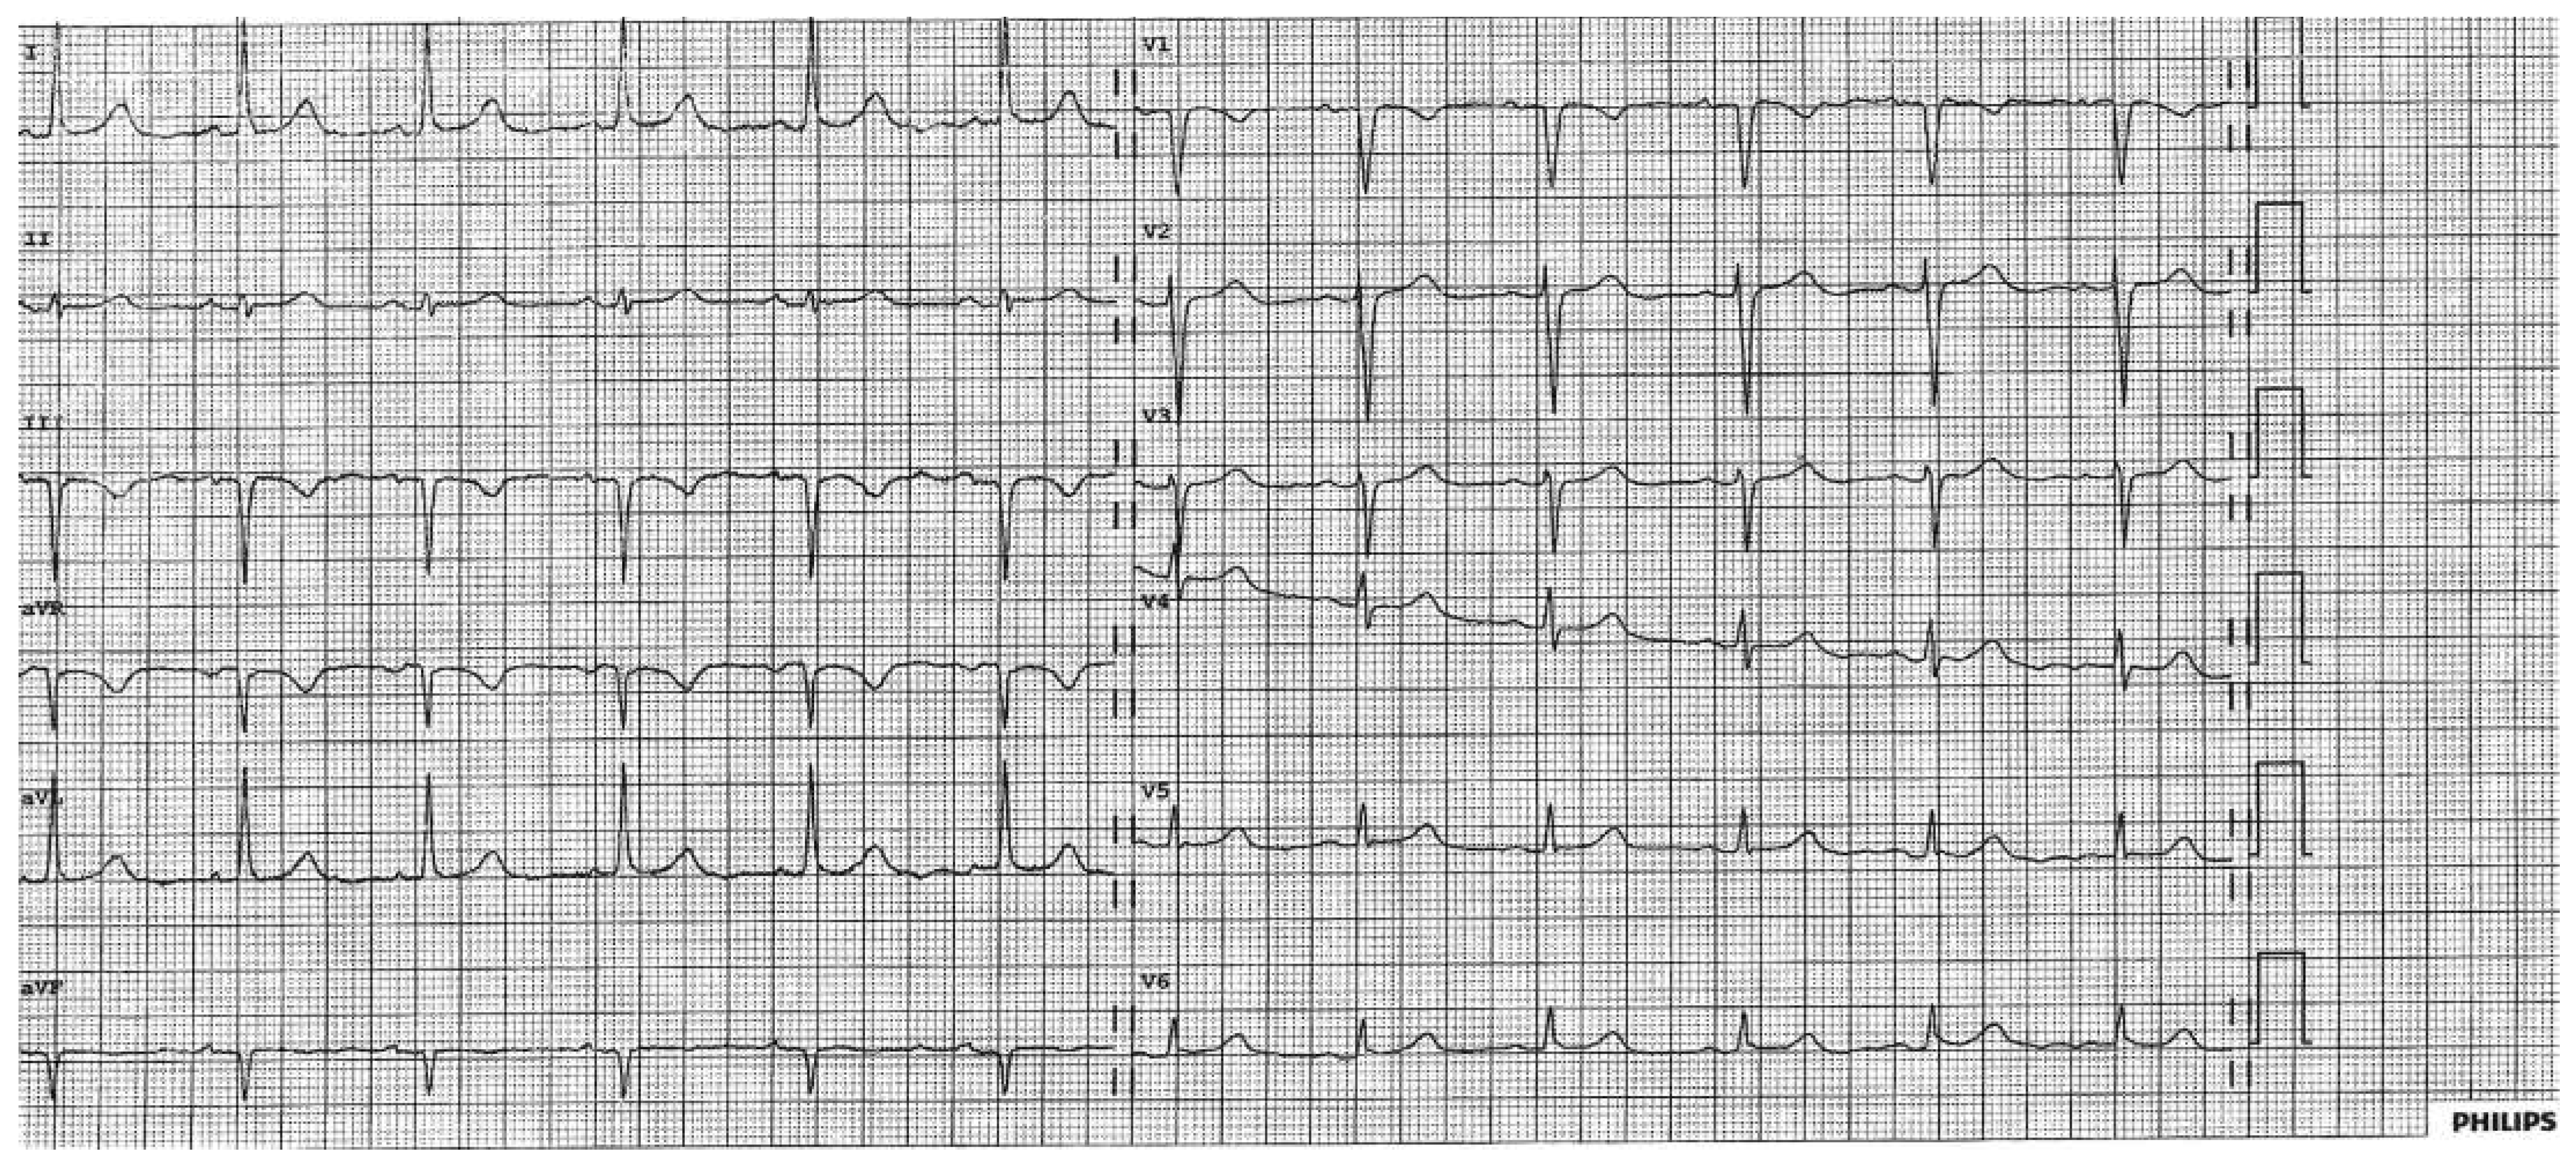

High-sensitivity troponin was slightly elevated at 0.024 µg/l (<0.014 µg/l) but showed no dynamic changes. Her only cardiovascular risk factor was hypertension. No ECG had been performed preoperatively. Echocardiography was normal, with a left ventricular ejection fraction of 60% and without left ventricular hypertrophy. Right ventricular function was normal and she had no pulmonary hypertension. We interpreted the low voltage as an artefact due to a shift of her anatomical heart axis and performed a modified ECG where the precordial leads were placed one (Figure 2) and two (Figure 3) intercostal spaces cranially. The modified ECG looked almost normal and virtually excluded another pathology.

Figure 2. By placing the precordial leads one intercostal space cranially the low voltage could be reduced.

Figure 3. By placing the precordial leads two intercostal spaces cranially the ECG normalised.